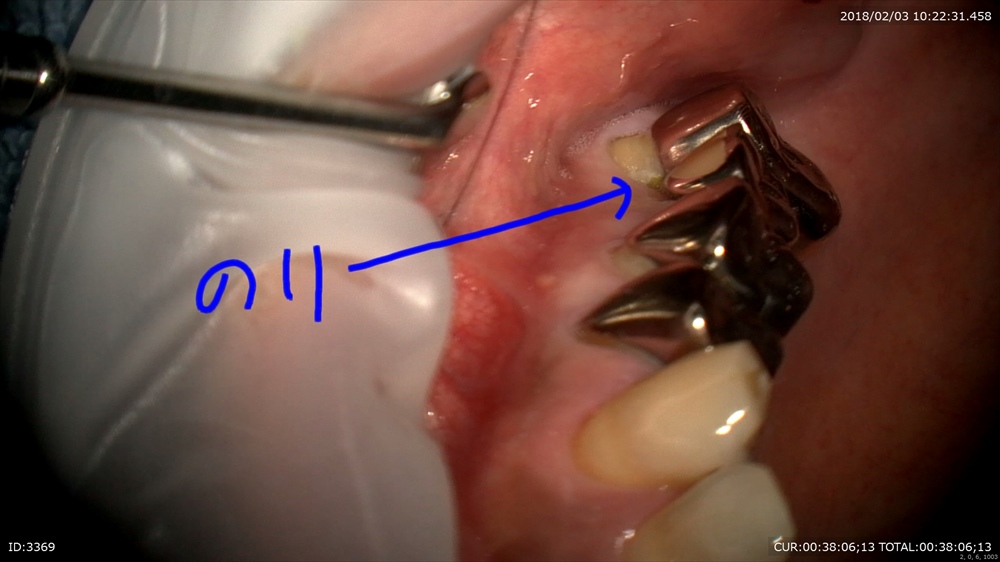

歯周病治療が終わり次のステップ。銀歯のブリッジが入っています。一見なにもない。症状もありません。歯科ドックでこの下に大きな虫歯が発見されました。本当でしょうか?のりが挟まっている。ということはここに隙間がある。=ここから細菌の進入が!!

わーーー

ほら。歯科ドック受けてよかったですね。

手前もぼろぼろ。でも救えます。まずは即席で仮歯を。ここが大切。むき出しになった歯は感染します。

次回から歯茎の調整にはいります。安心!!